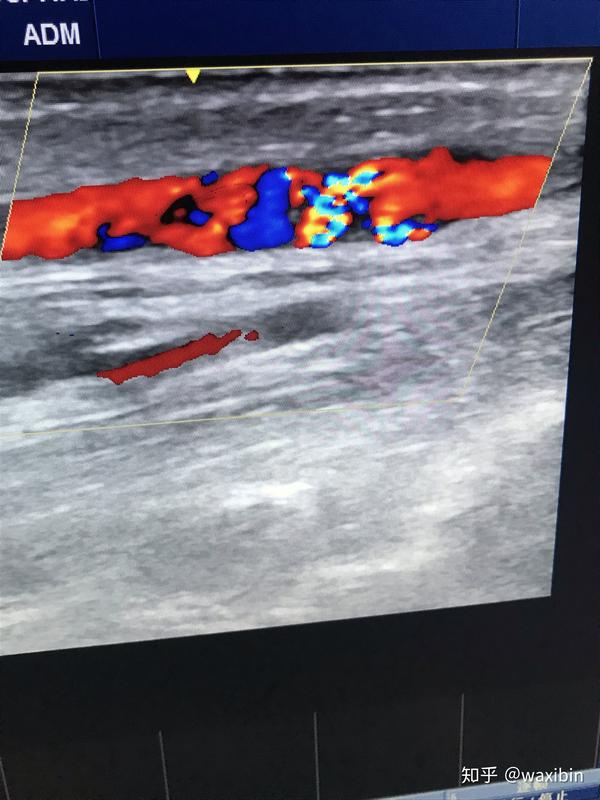

动静脉瘘血流

我们做了一个微导管造影,动静脉瘘的血流结构就分析的很清楚了.